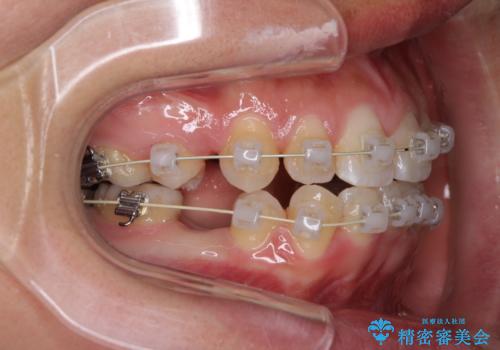

前歯が八重歯でガタガタ ワイヤーによる抜歯矯正

- 前歯のガタガタを主訴に来院されました。

前歯の重度のガタガタで、八重歯もある状態でした。

また右下の乳歯が残っており、永久歯が1本足りませんでした。

上顎両側と左下の前から4番目の歯と、右下の乳歯を抜歯して矯正することとなりました。

乳歯を抜歯することにより、通常よりは治療期間を要してしまいましが、前歯のガタガタもなくなりきれいな歯並びになったと喜んでいただけました。